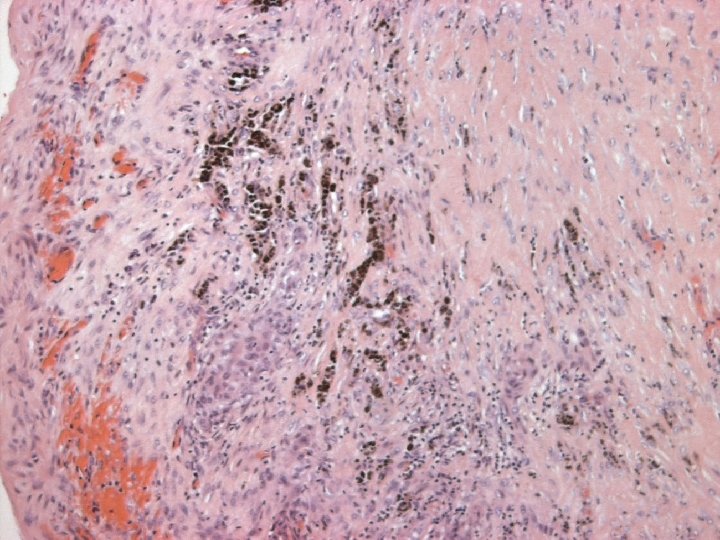

Variants of SCC of breast Keratinizing n Spindle cell n Acantholytic n

Micro n Similar to SCC at other sites n Cytoplasmic clearing in some

Micro The strongest evidence of a primary SCC of breast is presence of in-situ squamous carcinoma in duct or cyst lining.

pathogenesis Thought to arise from metaplastic squmous epithelium n Reddick proposes that squamous metaplasia arise from myoepithelial cells n Study on squamous metaplasia in a papilloma by IHC & EM.